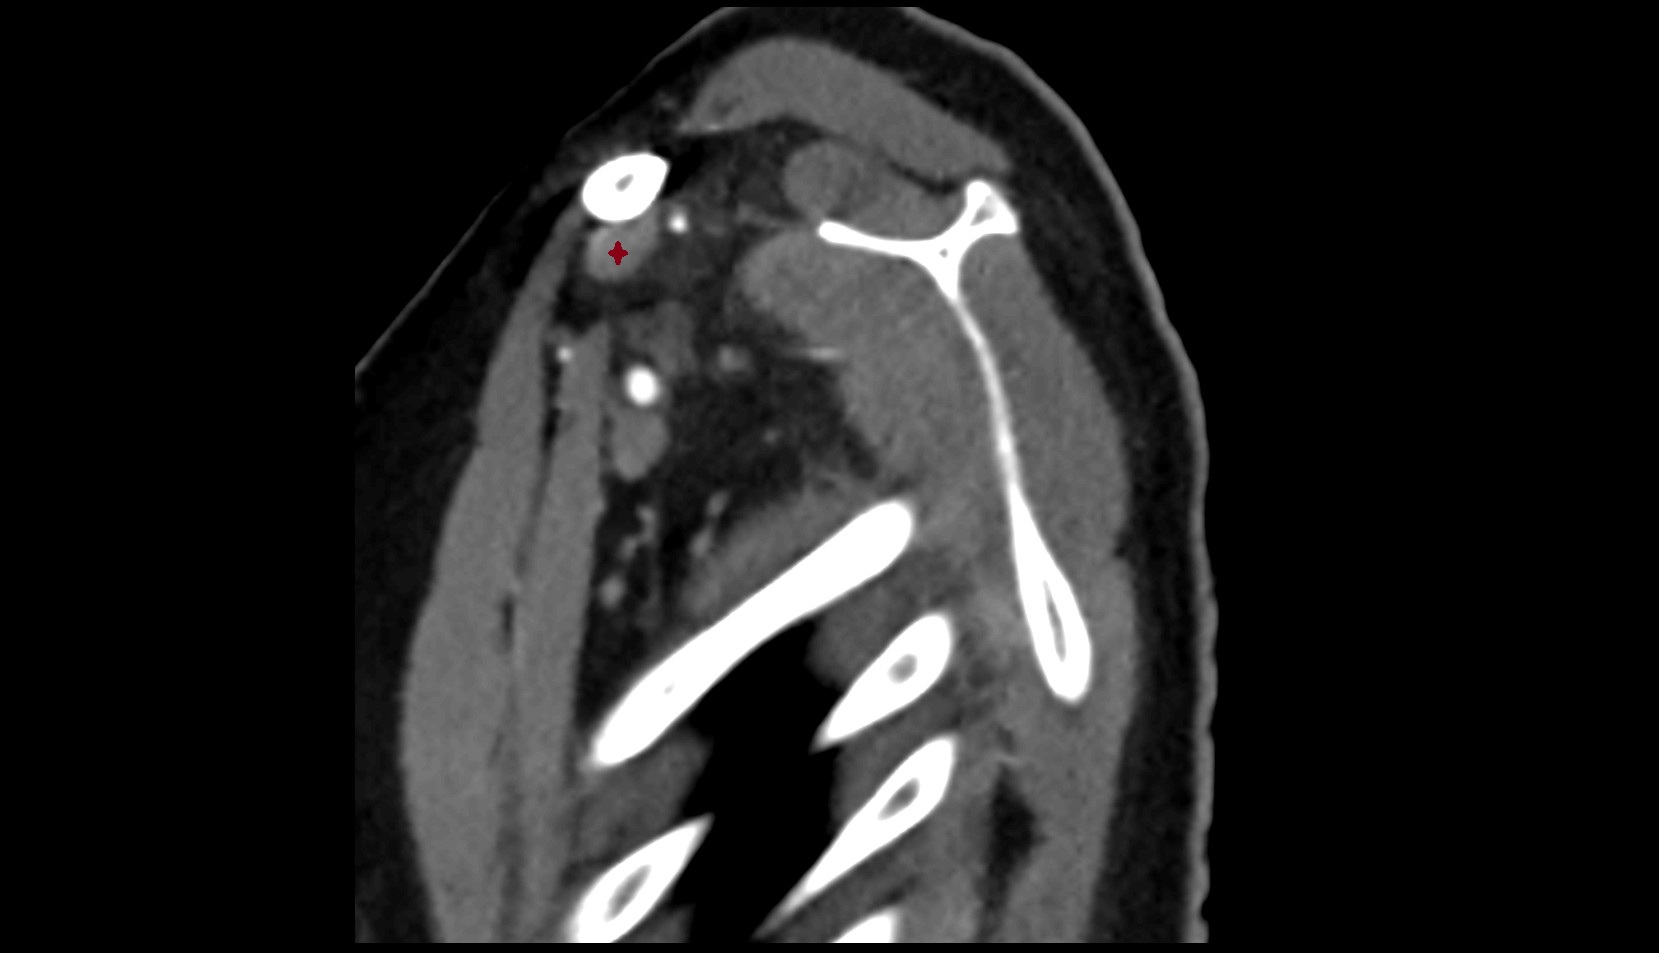

- Glenoid fossa

- Glenoid process of scapula

- Spine of scapula

- Acromion process of scapula

- Coracoid process of scapula

- Scapular body

- Humerus

- Head of humerus

- Shoulder joint (glenohumeral joint)